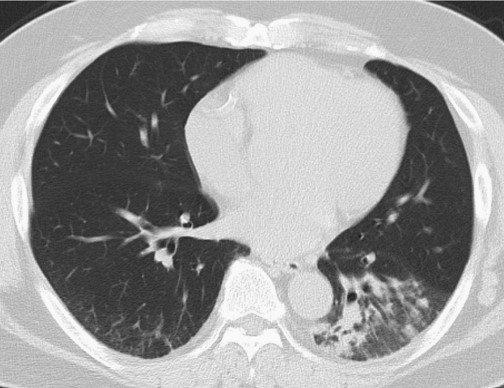

醫(yī)生試圖進(jìn)行腰椎穿刺,但因患者肥胖,手術(shù)終止。因癥狀較輕,給予患者每日小劑量氟康唑(100 mg po)治療,若效果不明顯則增加劑量。1個月后隨訪,患者表示咳嗽改善,CT顯示實變陰影明顯改善(圖3)。

圖3 高分辨率CT掃描顯示,1個月后患者左肺下葉實變改善